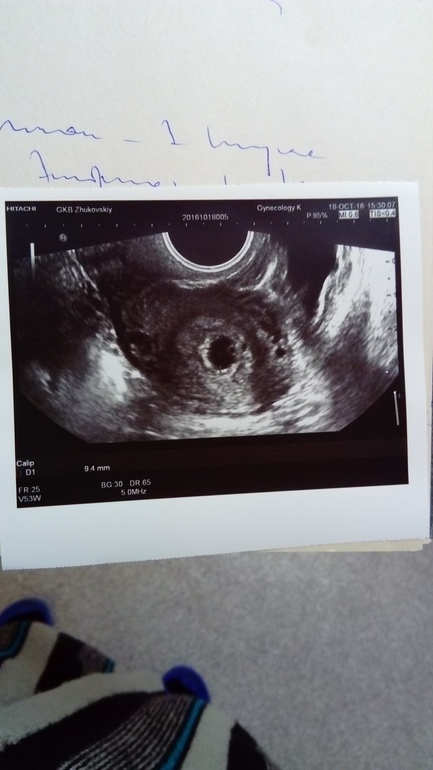

Через неделю на повторном узи увидели плодное яйцо без эмбриона, сказали что срок 3 недели, но срок очень разница с акушерским (акушерский 6-7недель)

Желточный мешочек уже виден и хорошо, значит и малыш там скоро появится. Может овуляция позже была и имплантация. Все будет хорошо верьте в малыша и ждите

Как нет, а в плодном яйце тогда что??? Даже на снимке видно что яйцо не пустое